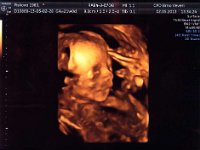

Jaro 2013